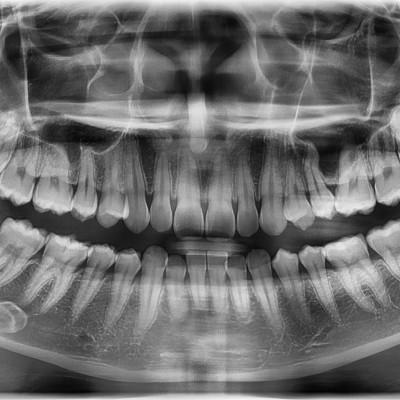

#28,38,48 사랑니 발치 #28,38,48 사랑니 발치 구강 외과 전문의가 당일 발치했습니다. ---------------------..

작성자 이턱이 작성일 01-29 조회 5